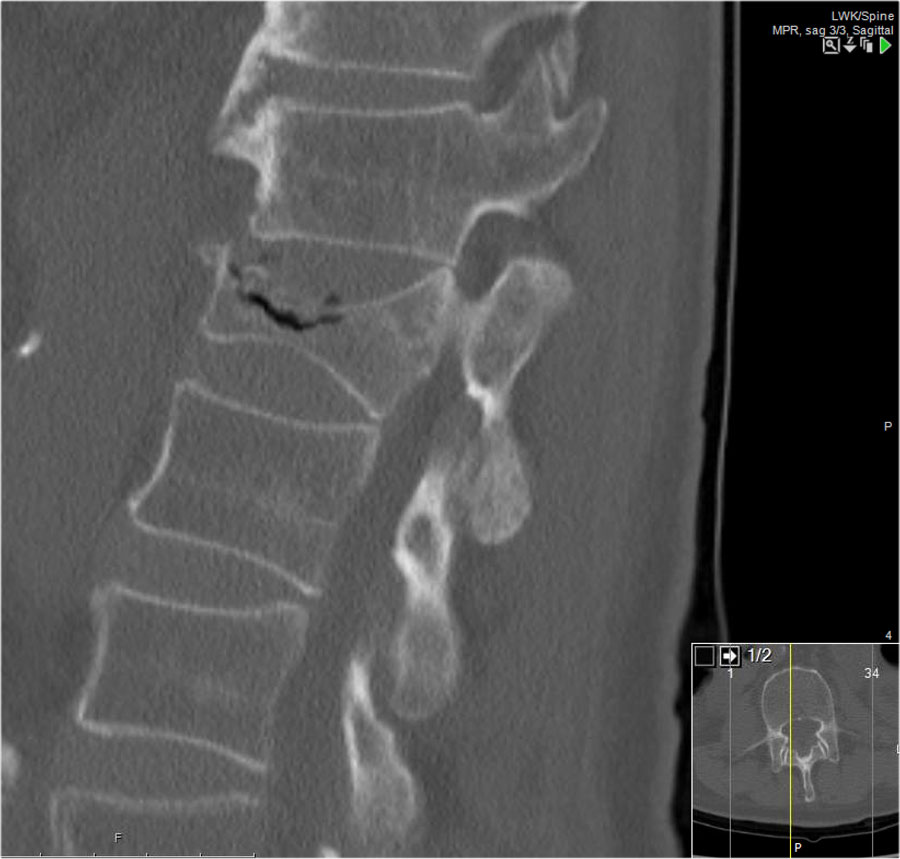

Các hình ảnh là của một bệnh nhân với hình ảnh cột sống tre điển hình do viêm cột sống dính khớp.

Sau khi ngã ngửa, không thấy gãy xương trên phim X-quang.

Tuy nhiên, CT cho thấy một đường gãy mảnh qua mặt trước thân đốt sống và cả qua mỏm gai.

Tiếp tục xem các hình ảnh MRI.